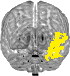

| Left Thalamus | 0 | 1% | 17 |

| Left Putamen | 2 | 14% | 151 |

| Left Hippocampus | 4 | 11% | 95 |

| Left Amygdala | 5 | 64% | 244 |

| Right Thalamus | 7 | 1% | 14 |

| Right Putamen | 9 | 14% | 151 |

| Right Hippocampus | 11 | 12% | 105 |

| Right Amygdala | 12 | 22% | 95 |

| Left VI | 114 | 2% | 35 |

| Right VI | 116 | 2% | 24 |

| Left Crus I | 117 | 3% | 64 |

| Right Crus I | 119 | 6% | 148 |

| Left Crus II | 120 | 0% | 2 |